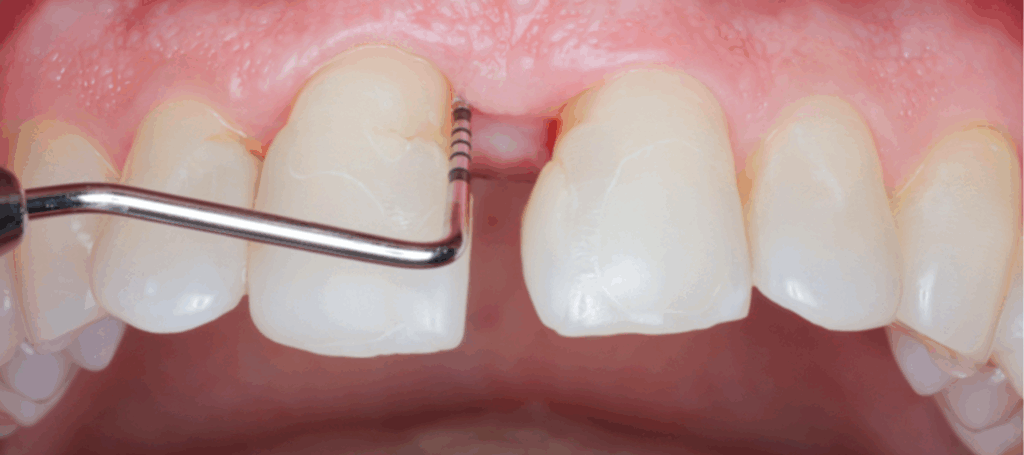

Moderne Präparationstechniken als Grundlage für zeitgemäße restaurative Behandlungskonzepte – eine Übersicht

Durch die Einführung der Adhäsivtechnik in Kombination mit einer fortwährenden Entwicklung von neuen zahnfarbenen Restaurationsmaterialien wurden die zahnärztlichen Präparationstechniken grundlegend verändert.